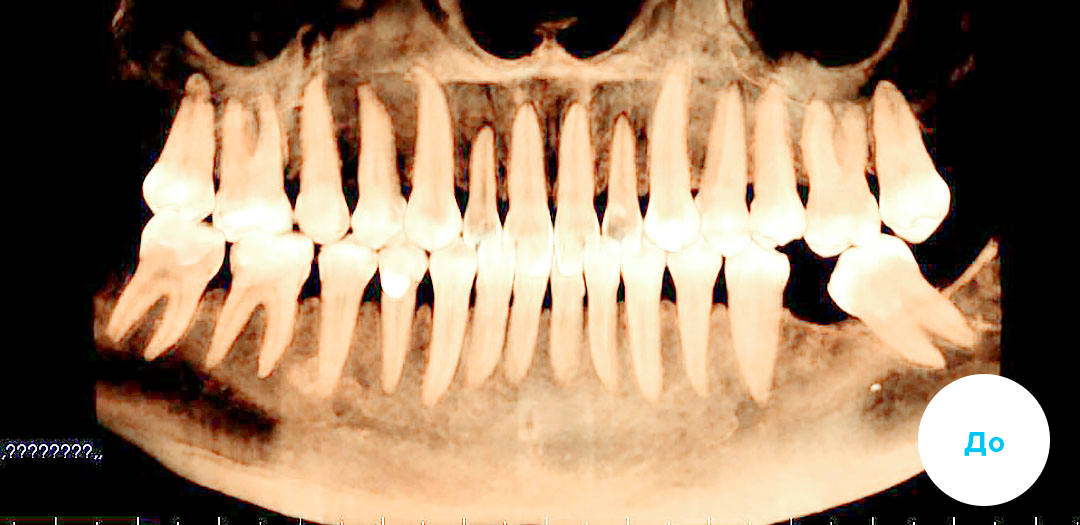

Работы специалиста